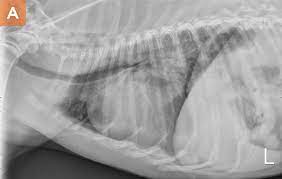

X rays are very helpful in the diagnosis of lung cancer in dogs. If you have lung cancer, it may be more difficult for your doctor to diagnose pneumonia. A white spot amidst the normal black lungs can therefore be a cancer, infection. Dog pneumonia or lung cancer. Pneumonia is a lung infection that leads to breathing difficulties and fluid in the lungs.

A definitive diagnosis of lung cancer requires a sample of tissue (biopsy). X rays are very helpful in the diagnosis of lung cancer in dogs. Primary lung cancer are frequently located in the caudal (towards the hind end of the pet) lung lobes, however can be located in any lung lobe and are usually a single mass in the lungs, unless the tumor has spread. If your dog has a chronic cough, you'll need to rule these out. The first of these possibilities could be investigated by bronchoscopy. A definitive diagnosis of lung cancer requires a sample of tissue (biopsy). The second kind of lung cancer in dogs is called metastatic lung cancer, which means the cancer originated somewhere else in the body, but has spread to the lung. Bacterial pneumonia is an inflammation of the lung usually caused by bacterial or viral infection but can be caused by inhalation of an irritant. The respiratory system consists of the large and small airways and the lungs. Lung cancer is actually the number one killer when it comes to cancers. But in some rare cases, it may be a lung cancer (primary or secondary). In both cases, you may have. Typical signs of bacterial pneumonia include fever, difficulty breathing, lethargy and coughing.

Primary lung cancer are frequently located in the caudal (towards the hind end of the pet) lung lobes, however can be located in any lung lobe and are usually a single mass in the lungs, unless the tumor has spread. My dog had pneumonia come on quickly this last august, we took her to the local er at 3am when we noticed her breathing labored and strange behavior. A white spot amidst the normal black lungs can therefore be a cancer, infection. Signs of the primary tumors in dogs. I haven't touched cigarettes a day in my life. Lung cancer often misdiagnosed as pneumonia urges requests for second medical opinions. Lung cancer is actually the number one killer when it comes to cancers. A definitive diagnosis of lung cancer requires a sample of tissue (biopsy). His appetite is basically normal though his blood work shows that he is anemic. 3 doctors agree send thanks to the doctor Other common respiratory diseases that might make you worried about cancer are …. Malignant tumors trigger inflammation in surrounding normal lung tissue, and they may obstruct. Pneumonia and lung cancer both affect the lungs but one is easily treatable and the other is potentially life threatening.